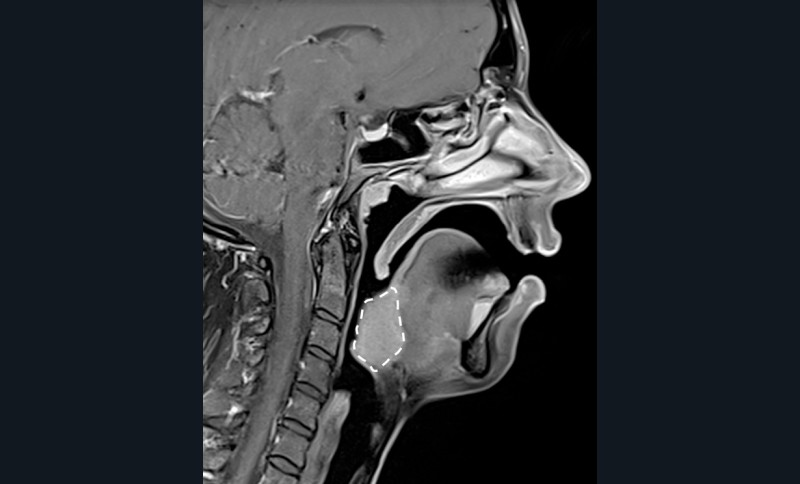

Le collapsus pharyngé à l’origine du SAOS peut résulter de mécanismes variés, souvent associés. L’hypertrophie des tissus mous (amygdales, base de langue, parois pharyngées) en est l’une des causes possibles, fréquemment liée au surpoids observé dans cette pathologie.

L’étroitesse squelettique peut également être impliquée (rétromandibulie, hyperdivergence, endognathie) [1] (fig. 1-4).

Il est nécessaire, pour la recherche d’un site obstructif…